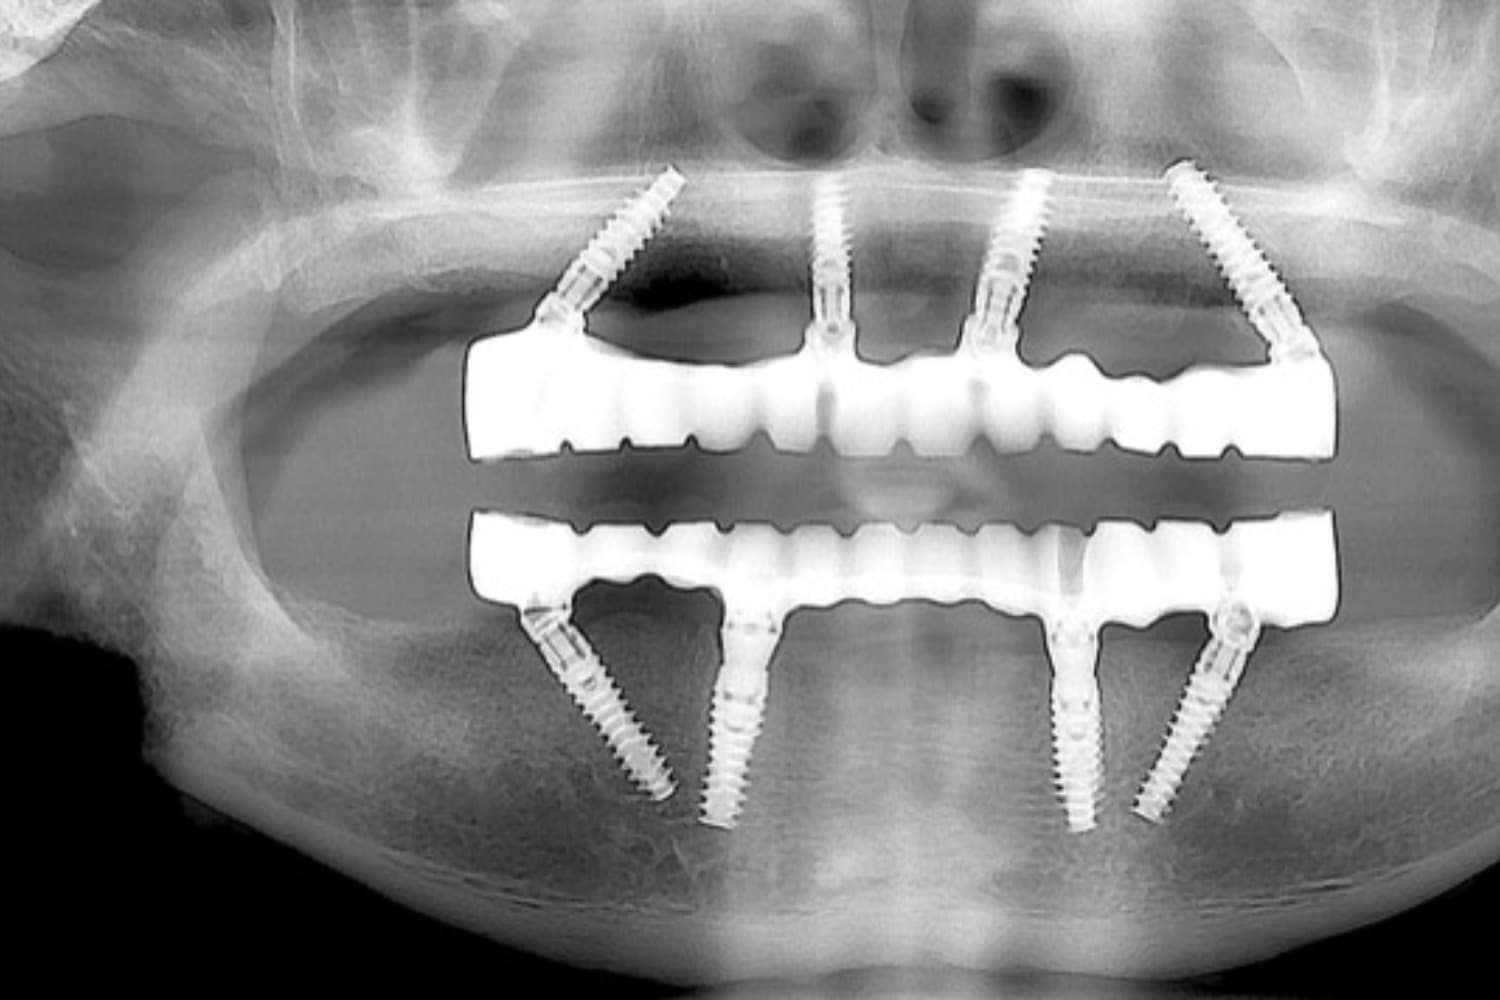

上下のインプラント治療

After

上下の保存できない歯を抜歯して、インプラント治療で咬合機能の回復をおこなう

60代

女性

8ヵ月

6回~7回

550万円